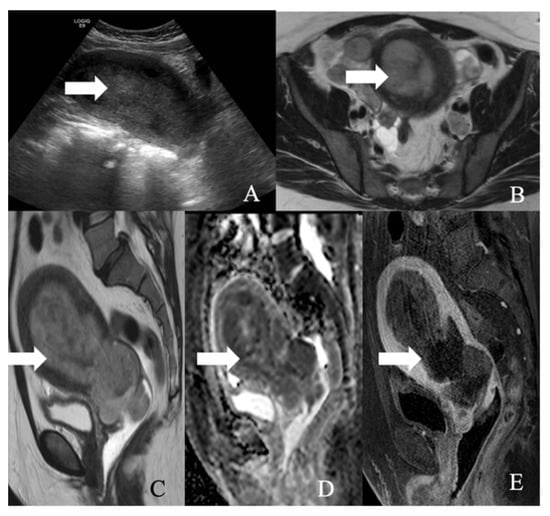

6. Endometrial NEN

NENs are a rare group of tumors constituting 0.8% of endometrial malignancies [96] (Figure 11). They are rare and usually adenocarcinoma or small cell cancers with a neuroendocrine differentiation [14]. Around 56% of patients present with advanced disease with abnormal uterine bleeding or metastatic symptoms [96]. The diagnosis is based on histology and imaging, and dilatation and curettage provide adequate biopsy tissue to determine histology. Like cervical carcinoma, non-specific imaging features of endometrial NENs do not allow for histological distinction. Most endometrial cancers have similar imaging characteristics: low to moderate signal on T2WI and hypointensity relative to the hyperintense enhancing myometrium on dynamic contrast-enhanced MRI sequences. With tumor growth, the histological appearance of endometrial NEC becomes identical to FIGO grade 3 endometroid carcinoma and undifferentiated carcinoma. In indeterminate imaging and histology cases, immunohistochemistry aids in the differentiation of endometrial malignancies. Most endometrial NEC demonstrates a diffuse expression of ≥2 markers such as neuron-specific enolase, synaptophysin, chromogranin, or CD56, whereas endometroid and undifferentiated carcinomas exhibit focal positivity for neuroendocrine markers. Hence, to diagnose NEC, more than 20% of the tumor cells need to be positive for at least two of the markers [97]. The expression of p16, p53, and TTF1 by both NEC and endometroid carcinoma makes these markers unreliable and requires further studies to determine their accuracy.

Nonetheless, when a highly aggressive endometrial tumor is diagnosed, NENs should be suspected. Table 10 and Figure 12 describe the FIGO staging, while Figure 13 demonstrates the treatment algorithm of endometrial NEN. Endometrial NECs are aggressive carcinomas associated with an overall survival of 22 and 12 months in stages I–II and III–IV, respectively [57]. According to Schlechtweg et al., the five-year and median survival for patients with endometrial NEC are 38.3% and 17 months from diagnosis. Compared to other endometrial carcinomas, NEC has an increased risk of death with a hazard ratio of 2.32 (95% CI: 1.88–2.88%) [96].